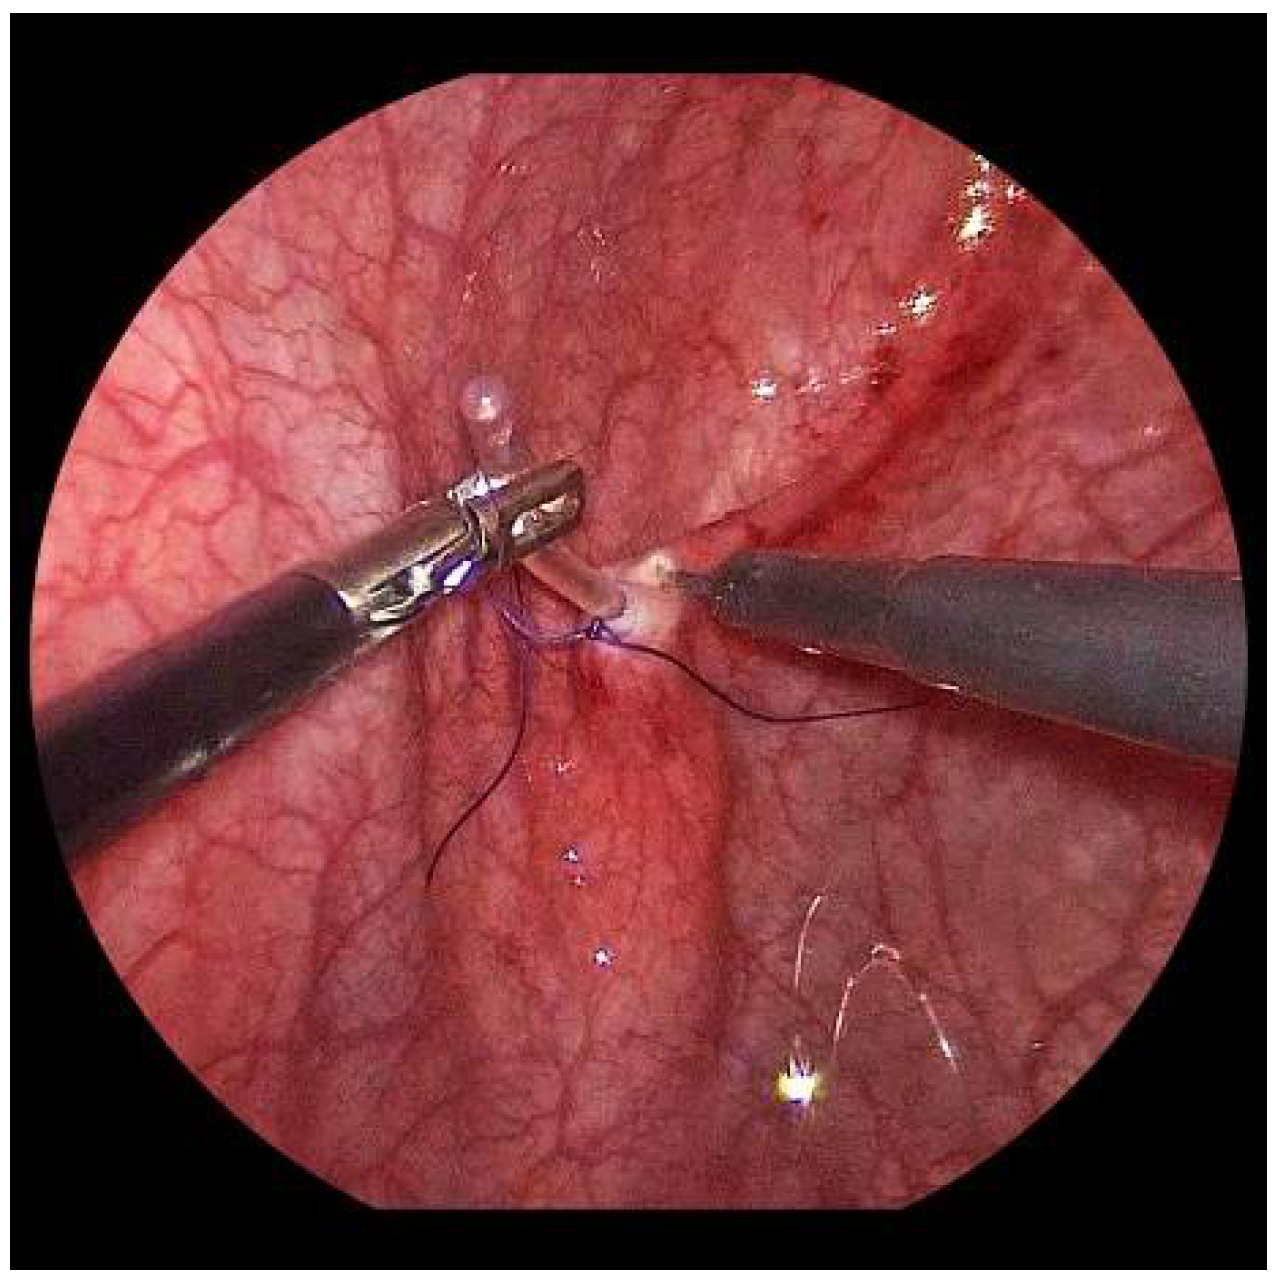

Now, the ureter is intubated with a 3 or 4 Fr. silicone tube, followed by subtle circumferential electrical mucosa incision with a fine dissecting needle (Figure 3). The ureteral release is continued using an electrical hook for at least 4 to 6 cm until it can be positioned without tension to the opposite ostium (Figure 4). Duplicate ureters are intubated twice and mobilized together. If bilateral, the submucosal tunnel is created between the two ostial incisions. If not, an additional mucosal incision is made 1 cm canially of the opposite regular ostium (Figure 5).

Figure 3.

For a left-sided VCUR, the ostium is circumferentially incised with a fine needle while gently pulling on the intubated left ureter.